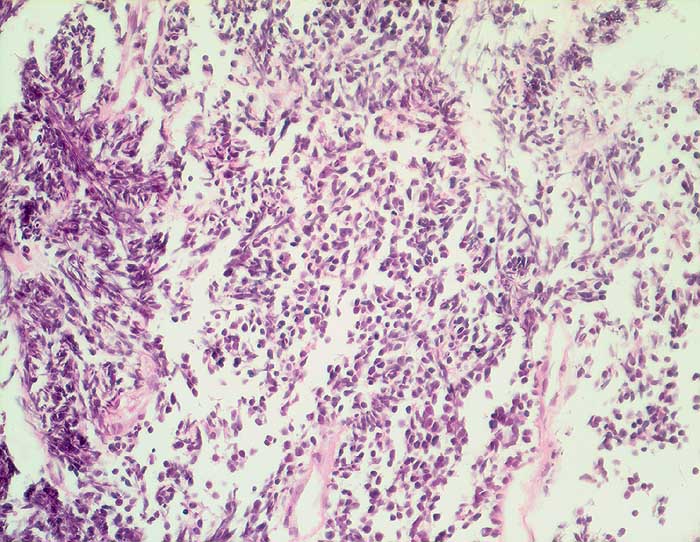

Kleinzelliges Bronchuskarzinom

Der Nachweis des kleinzelligen Karzinoms gelingt im Sputum meist leichter als im Bronchialsekret. Im Bronchialsekret sind die Tumorzellen oft zwischen Flimmerzellen und Entzündungszellen versteckt, während die stark hyperchromatischen Kerne im Sputum schon bei schwacher Vergrösserung ins Auge fallen. Die fast nacktkernigen Zellen liegen einzeln oder bilden schmale zeilenförmige Verbände und Haufen. Innerhalb der Verbände schmiegen sich die Kerne eng aneinander (=molding). Die Kerne sind zwei- bis dreimal so gross wie Lymphozyten. Im Sputum erscheinen die Karzinomzellen kleiner als im Feinnadelpunktat, Bürstenabstrich oder Bronchialsekret.

Basalzellen sind monomorpher und bilden kleine, regelmässige kompakte Verbände. Lymphomzellen liegen stets einzeln. Feindisperse Chromatinverteilung und zeilenförmige Verbände sprechen gegen ein Lymphom. In Zweifelsfällen erfolgt die Unterscheidung immunzytochemisch (Panzytokeratin und CD45).

Das ersten Beispiel zeigt ein Bronchialsekret, das zweite eine Bronchialbürstenzytologie.